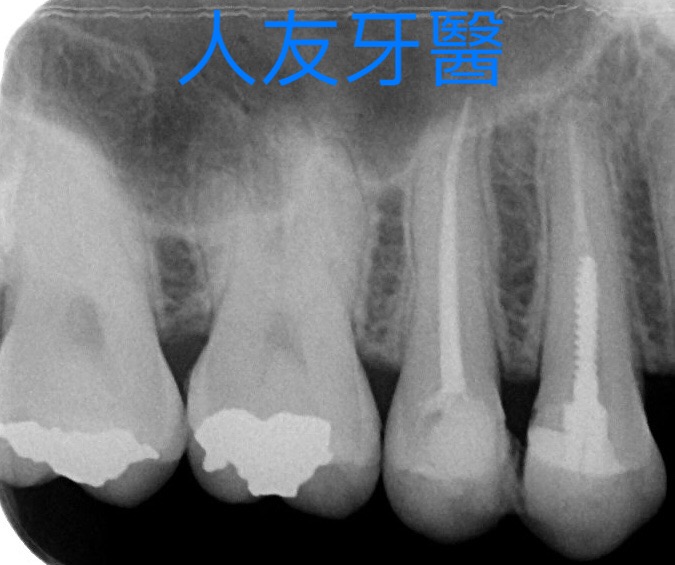

3BDCE4FA-1685-42A9-80EA-79E5A978E730